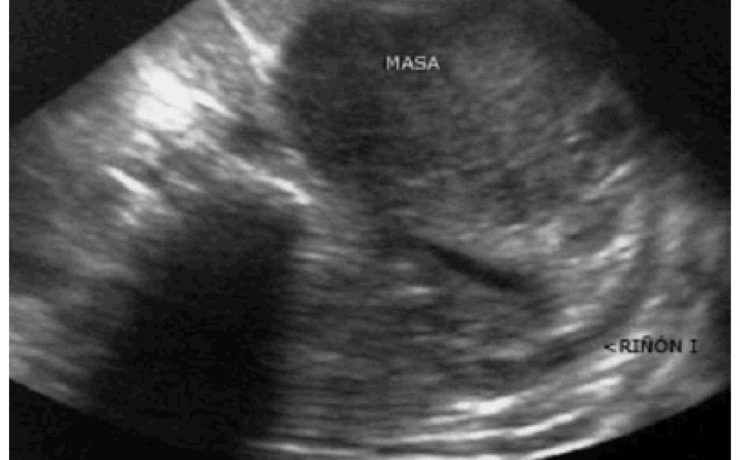

Se realizó un estudio descriptivo prospective, evaluando a 336 pacientes operados de colecistitis aguda o crónica por vía laparoscópica. Todos los pacientes fueron evaluados con ecografía abdominal al menos 7 días antes de la cirugía por un médico radiólogo experto y de acuerdo a varios parámetros se dividen en 3